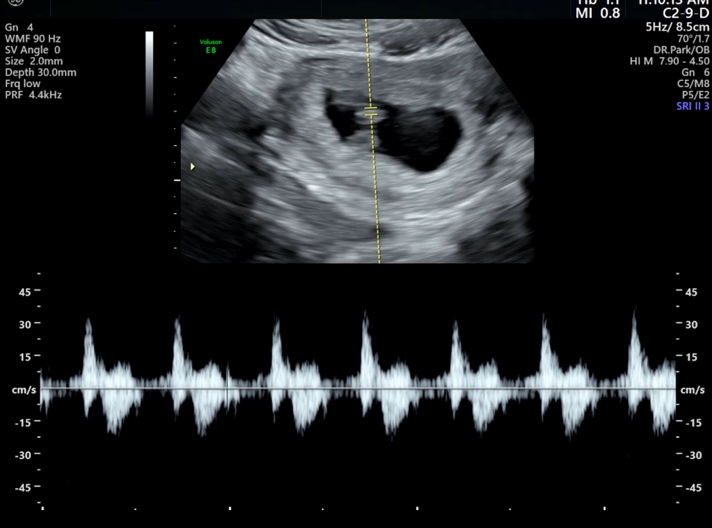

임신일기 : 10주차 ~ 16주차 (임신 초기 감기몸살, 태아보험 가입, 기형아검사, 갈색 냉, 짱구맘 성별확인, ?태몽, 새해 우정여행)

?? 나의 트롱이 일지 10주 ~ ?? #10주5일 |2024.01.12 10주차에 몸이 으슬으슬하고 잘 안걸리...